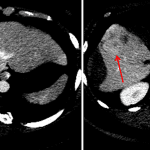

- Intermediate attenuation right hepatic subcapsular collection measuring 14 x 5 x 16 cm, which is in continuity with an intrahepatic collection with similar imaging characteristics in the inferior aspect of the right hepatic lobe measuring 6 x 6 x 7 cm

- Ill-defined hyperenhancing hepatic lesions in segments 5 and 8, with enhancing soft tissue extending along the periphery of the intrahepatic collection

- Ruptured hepatic adenoma

Large hepatic subcapsular hematoma measuring 14 x 5 x 16 cm, which is in continuity with an intrahepatic hematoma in the inferior aspect of the right hepatic lobe measuring 6 x 6 x 7 cm. Adjacent to the parenchymal hematoma, there are ill-defined hyperenhancing hepatic lesions in segments 5 and 8, which are favored to represent adenomas in the absence of history of malignancy and are the likely source for hemorrhage. Recommend surgical evaluation and followup liver protocol MRI for further assessment.